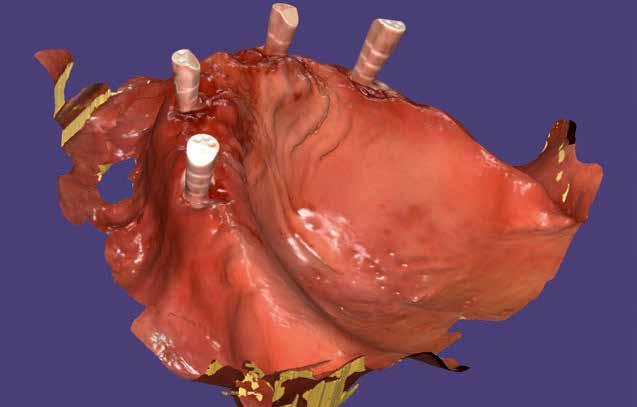

2. kép: A beszkennelt scanbody-k mutatják a Bicon implantátumok helyzetét.

A páciens évekkel ezelőtt két mukozális megtámasztású kivehető fogsort kapott. Az atrófia következtében ezek már nem rögzülnek megfelelően. Implantátumokat terveztünk pillérként. A csekély csontkínálat és az egyszerűbb kezelhetőség okán négy rövid implantátumot (Bicon, Bosten) helyeztünk be. Végleges pótlásként teleszkóp elhorgonyzású redukált alaplemezű kivehető fedőfogsort terveztünk. A fogorvos intraorális szkennerrel beolvasta az alsó és felső állcsontot. Ehhez becsavarta az implantátumokba a megfelelő scanbody-kat (digitális lenyomatvételi fej - a ford.) (rövid UA-Scan-post, Bicon, 2. kép). Mivel a régi fogsorral komfortosnak érezte a harapást a páciens, ez segített a harapásregisztrációban. A helyzet rögzítésére vesztibulárisan beszkennelte az orvos a behelyezett fogsorokat. Végül a két fogsort szájon kívül is, egészében beolvasták a Medit IO-szkennerrel (Szöul). Utoljára portréfotó

készült. Minden így nyert adatot interneten a laboratóriumba küldtek. A végleges elkészítéséig a páciens hordja tovább régi fogsorait. Nem volt szükség további találkozásokra sem ideiglenes fogsor készítéséhez, sem a harapásregisztrációhoz és laborban készített sablonok próbájához sem.

Fogtechnikai labor:

A laboratóriumban az összes adatot összefűztük egy „digitális pácienssé” a darmstadti exocad DentaCad rendszerében. Az állcsontokat a vesztibuláris fogsorbeolvasással illesztettük térben egymáshoz (3. kép). Az implantátumok helyzetét a fejek mutatták meg. A külön beszkennelt fogsorokat pedig mock-up-ként tudtuk használni a tervezés során (4. kép). A páciens portréját rávetítettük a frontra, így segítve az esztétikai ellenőrzést (5. kép)

Az állcsontok 3D adataiból digitális munkamintákat készítettünk, majd kinyomtattuk ezeket DLP-3D nyomtatóval (6. kép). A digitális mintakészítés technikai analóg implan-

6. kép: A 3D nyomtatású munkaminta.